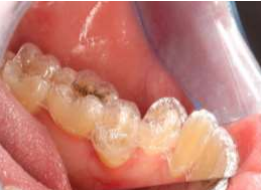

Fig. 1: Tooth 35 does not fit well with the aligners

Fig. 2: Fit problems in region 35

Fig. 3: Fixing braces of tooth 36-34 to straighten tooth 35 more quickly